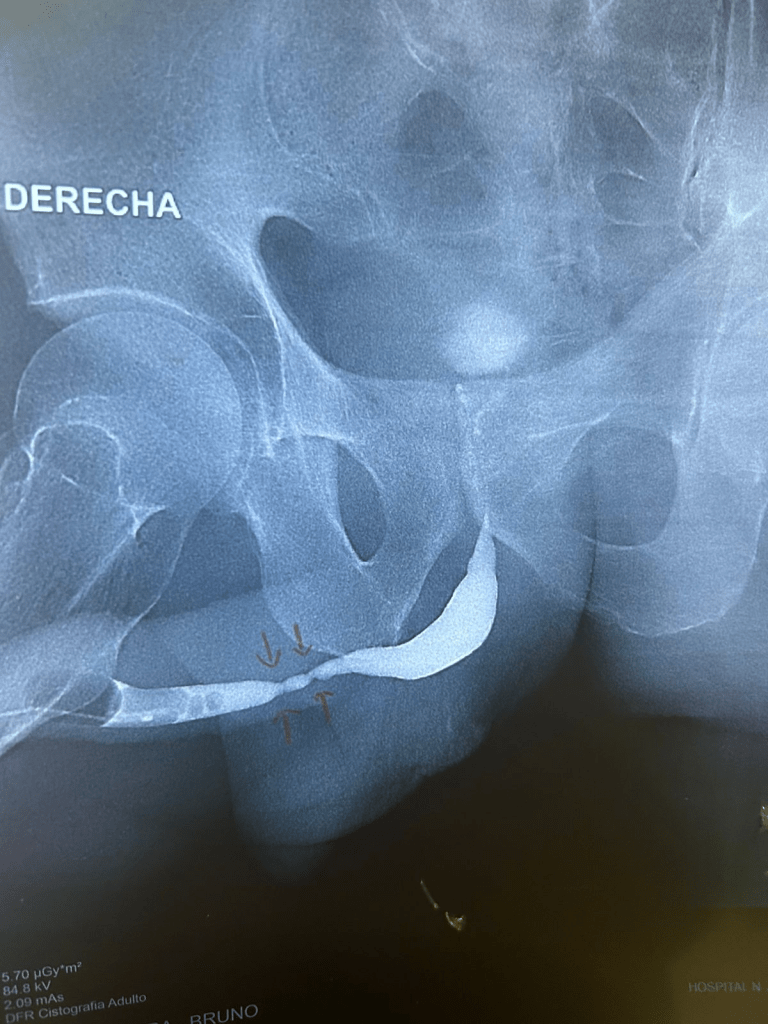

Lesión uretral asociada a fractura pélvica

- Diagnóstico preoperatorio: uretrografía retrógrada + cistouretrograma miccional y/o cistoscopia retrógrada y anterógrada. (Recomendación moderada; Nivel de evidencia: Grado C)

- Manejo definitivo: uretroplastia diferida (no endoscopia diferida). (Opinión de experto)

- La reconstrucción debe planificarse sólo tras estabilización de las lesiones graves. (Opinión de experto)